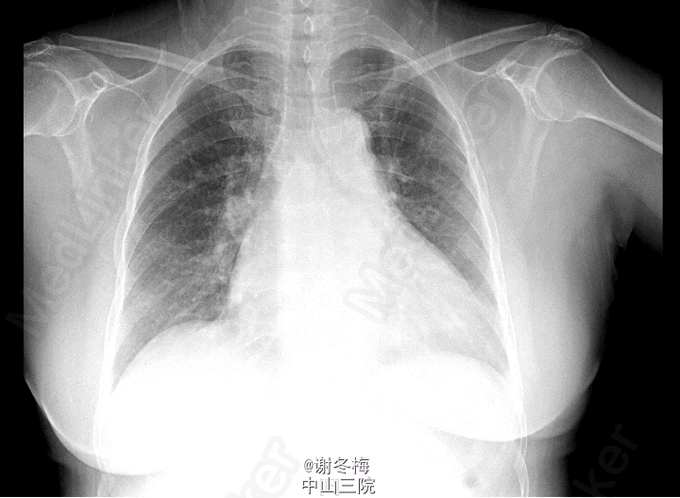

查体:BP108/69mmHg,神清,呼吸平顺,颜面、眼睑无浮肿,皮肤粘膜无苍白,甲状腺Ⅰ度肿大,质软,无触痛,未扪及结节,心率104次/分,律齐,各瓣膜听诊区未闻及明显杂音,双肺呼吸音粗,未闻及干湿性啰音,腹膨隆,腹软,无压痛、反跳痛,双足背动脉搏动可,双下肢无凹陷性浮肿。 辅查:2015-3-16我院行彩超心脏:左房、左室增大(左心房41mm,左室舒张末容积60mm),右房稍大,左室壁普遍性运动减弱,左心功能减低(EF 32%),二尖瓣反流(中重度)。三尖瓣反流(中重度)。主动脉瓣反流(轻度)。肺动脉高压(轻度)。心包积液(微量)。 Holter:1、窦性心律,2、偶发房性早搏,3、频发多源发室性早搏伴成对室性早搏(1836个),4、T波改变。 冠脉CT:1.LM近分叉处狭窄约20%(非钙化斑块);LAD近段钙化斑块,管腔未见狭窄;余冠状动脉CTA未见异常。2.左肺炎症。